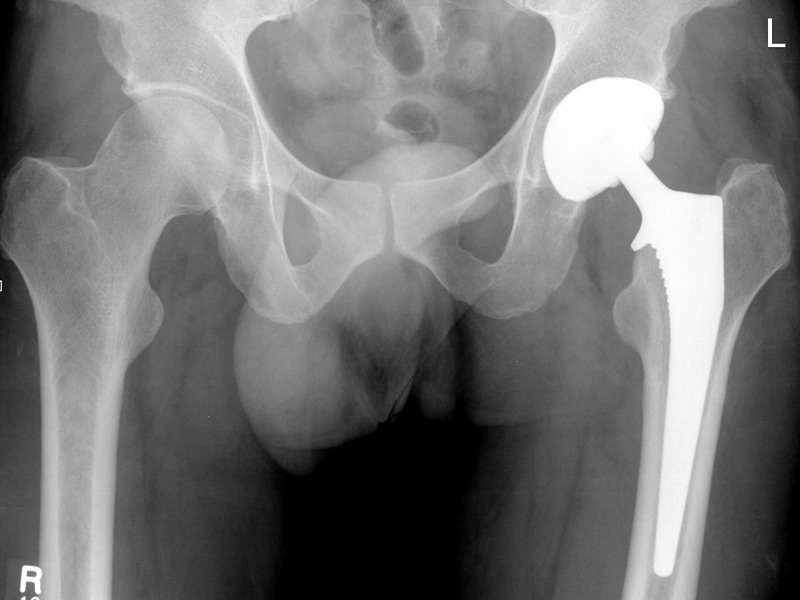

Do I need a new hip

Do I need a hip replacement

A lot of our patients, especially those over 50 ask us about hip pain. Typically, they are worried if they are going to need a hip replacement. The oxford hip socre is an easy test, that gives a good idea of whether a hip is likely to need replacing.

The test involves 12 questions with multiple choice answers and points are deducted from your score depending on how severe the problem is. The maximum score is 60 and a score of 19 or below indicates that a hip replacement should possibly be considered.

A score this low may indicate severe hip arthritis. It is highly likely that you may well require some form of surgical intervention, contact your GP for a consult with an Orthopaedic Surgeon. Chiropractic care is essential when the hip is severely degenerate to maintain as much movement and activity as possible before a hip replacement is performed.

A score of 20 to 29 may indicate moderate to severe hip arthritis. See your Chiropractor for an assessment and x-ray. Your Chiropractor may consider a referral to an Orthopaedic Surgeon. Chiropractic care will help relieve the pain from the hip until surgery can be performed.

A score of 30 to 39 may indicate mild to moderate hip arthritis. Consider seeing your Chiropractor for an assessment and possible x-ray. You may benefit from non-surgical treatment, such as exercise, weight loss, and /or anti-inflammatory medication. If you look after this joint now you can prolong its life and avoid the surgeons knife.